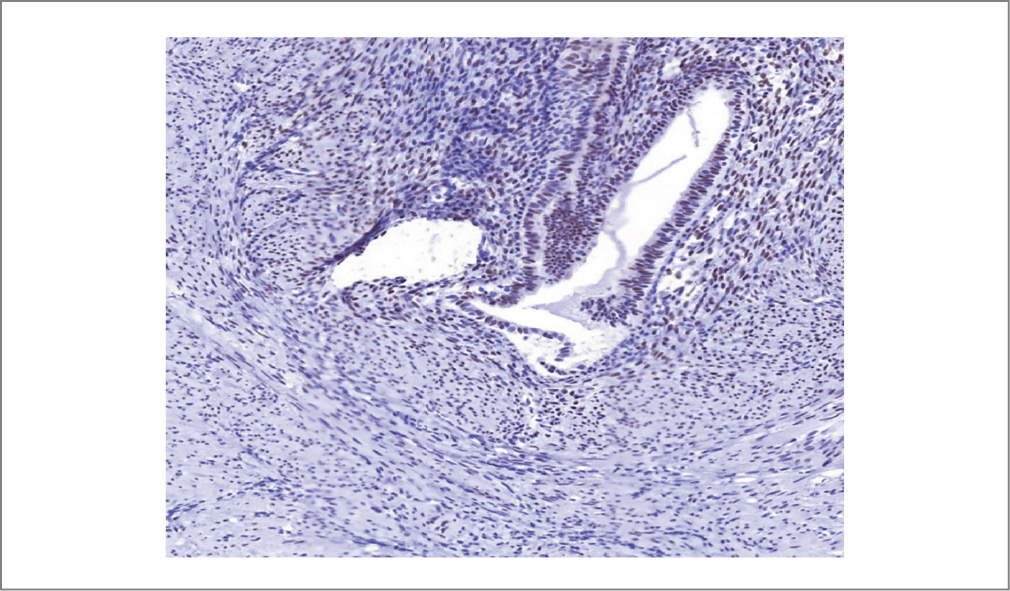

Рис. 6. Экспрессия ER в железах эндометрия. Иммуногистохимия. ×180.

Fig. 6. ER expression in the endometrial glands. Immunohistochemistry. ×180.

Результат патоморфологического исследования биопсийного материала (серо-розовая ткань плотно-эластичной консистенции, на разрезе белесоватого цвета, слоистого вида) представлен фрагментами новообразованной ткани, хаотично располагающимися мышечными волокнами с неравномерным разрастанием соединительной ткани, с фокусами соединительной ткани с участками, представленными эндометриоидными железами и стромой, по периферии – макрофаги, фагоцитирующие гемосидерин (рис. 3). При иммуногистохимическом исследовании выявлена умеренно выраженная экспрессия рецепторов эстрогена и прогестерона в клетках и железах эндометрия (рис. 4–8).